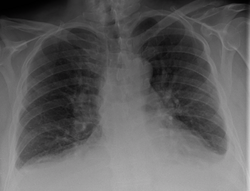

Chest X-rays are frequently used to aid in the diagnosis of CHF. In a person who is compensated, this may show cardiomegaly (visible enlargement of the heart), quantified as the cardiothoracic ratio (proportion of the heart size to the chest). In left ventricular failure, there may be evidence of vascular redistribution ("upper lobe blood diversion" or "cephalization"), Kerley lines, cuffing of the areas around the bronchi, and interstitial edema. Ultrasound of the lung may also be able to detect Kerley lines.[38]

Congestive heart failure with small bilateral effusions.